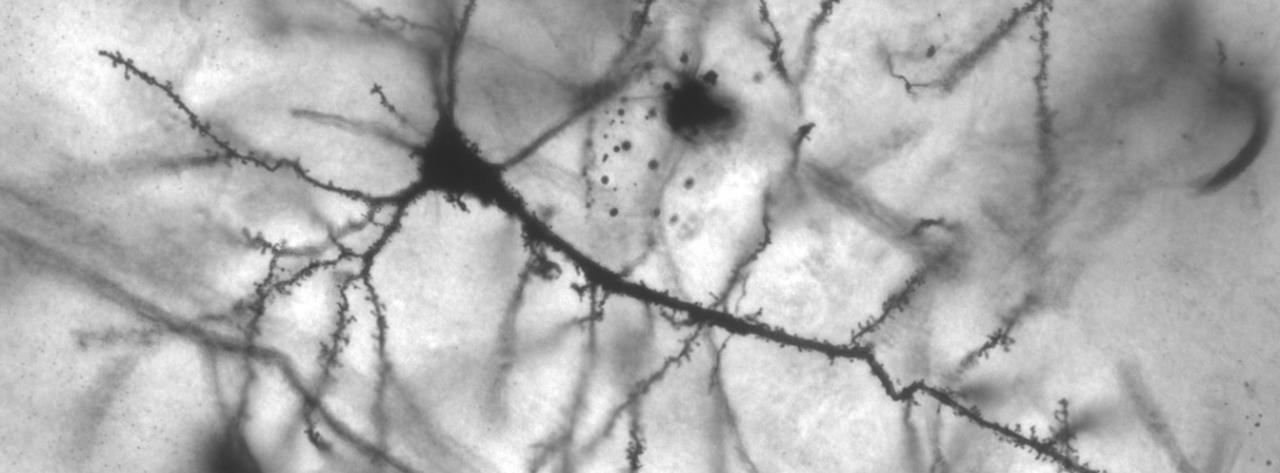

És doctor en Biologia i professor i investigador de Genètica a la Universitat de Barcelona. La seva trajectòria professional, centrada en la genètica del desenvolupament i la neurociència, i la seva relació amb el comportament i els processos d’aprenentatge, s’ha desenvolupat principalment a Barcelona. Fou investigador a la Universitat d’Oxford, i ha realitzat estades a la Universitat d’Innsbruck (Àustria) i a l’European Molecular Biology Laboratory de Heidelberg (Alemanya). Imparteix classes de diverses matèries del camp de la genètica, als màsters de Formació del professorat i de Comunicació especialitzada, i en diversos postgraus i màsters en neuroeducació. Ha publicat seixanta articles científics en revistes especialitzades.